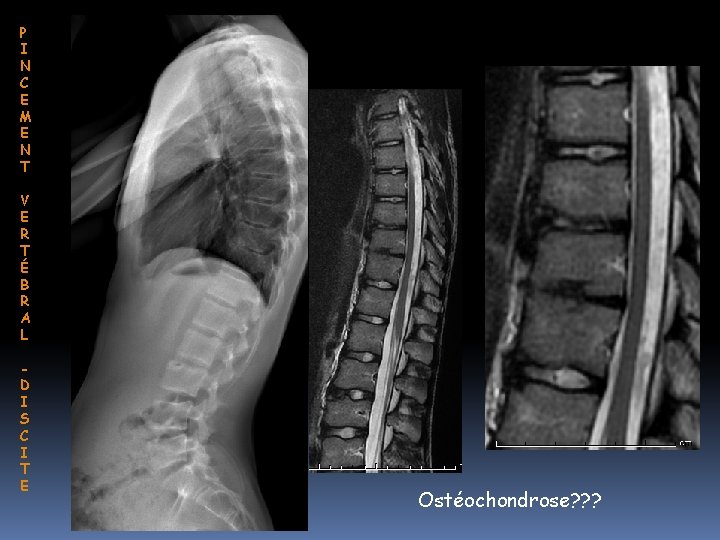

P I N C E M E N T V E R T É B R A L D I S C I T E Ostéochondrose? ? ?

P I N C E M E N T V E R T É B R A L D I S C I T E Le disque intervétébral Nucleus pulposus avasculaire, riche en polysaccharides hydrophyle Diffusion à partir de l’os trabéculaire à travers de fin canaux creusés dans le cartilage hyalin 2 hypothèses physiopathologiques possibles ne s’excluant pas • Contraintes biomécaniques ↓ Polysaccharides deshydratation • Lésions des canaux déshydratation du disque